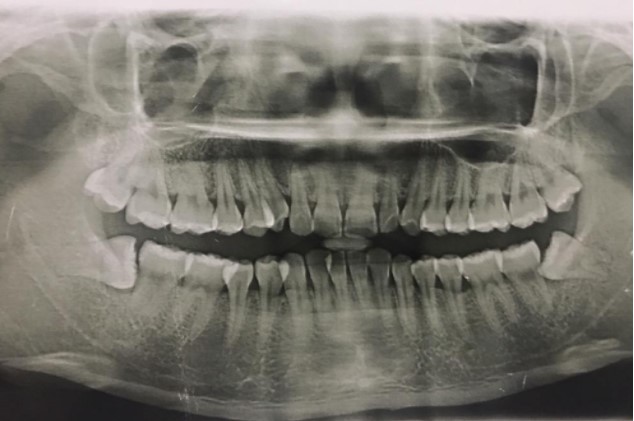

患者,男,38歲。上前牙變色1年,自述上前牙5年前受過(guò)外傷,唇側(cè)傾斜,檢查可見(jiàn)左上1牙冠變色,牙冠缺損近1/2,牙髓測(cè)試無(wú)反應(yīng),X線根尖片顯示患牙無(wú)明顯異常,全景片顯示雙側(cè)下頜智齒近中阻生,之前有發(fā)炎化膿病史,目前無(wú)咀嚼不適。口腔其余無(wú)異常。

檢查情況及X線片見(jiàn)下圖: